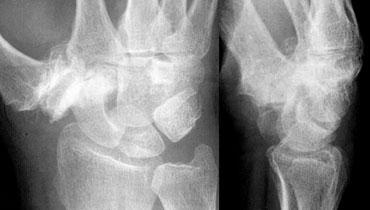

Phân tích:

1. Gãy xương thuyền và mỏm trâm trụ.

2. Cung I và II bị gián đoạn tại khớp LT (nguyệt-tháp).

3. Có sự song song giữa xương nguyệt và cực gần xương thuyền với xương quay.

4. Xương thuyền bị ngắn lại (foreshortened), cho thấy nó đang nghiêng và di chuyển về phía lòng bàn tay.

5. Tất cả các xương cổ tay còn lại đều có tính song song, ngoại trừ xương nguyệt, cực gần xương thuyền và xương quay.

Mặc dù đây có thể là trật khớp quanh nguyệt, nhưng chỉ dựa vào tư thế PA rất khó để phân biệt đây là trật khớp xương nguyệt hay trật khớp quanh nguyệt. Hình dạng tam giác của xương nguyệt có thể là kết quả của việc chỉ nghiêng đơn thuần hoặc trật khớp kèm nghiêng.

Trật khớp quanh nguyệt kèm gãy xương thuyền và mỏm trâm trụ. Đầu mặt lòng của xương nguyệt cũng bị gãy (xem vòng tròn).

Cùng ca lâm sàng với tư thế nghiêng được hiển thị thêm.

Bây giờ chúng ta thấy rõ ràng đây là trật khớp quanh nguyệt.

Vì vậy, hình dạng tam giác của xương nguyệt là kết quả của việc nghiêng đơn thuần.

Trên tư thế nghiêng, quan sát thấy gãy đầu mặt lòng của xương nguyệt. Do đó, bệnh nhân này có nguy cơ trật khớp tái phát.